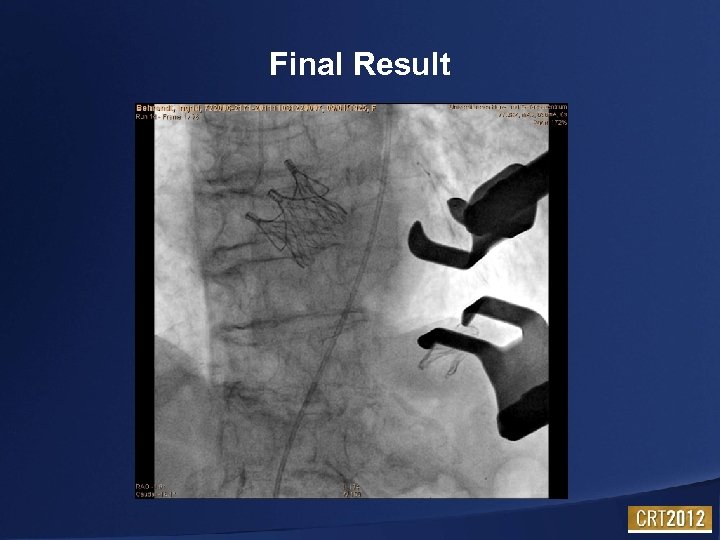

Final Result